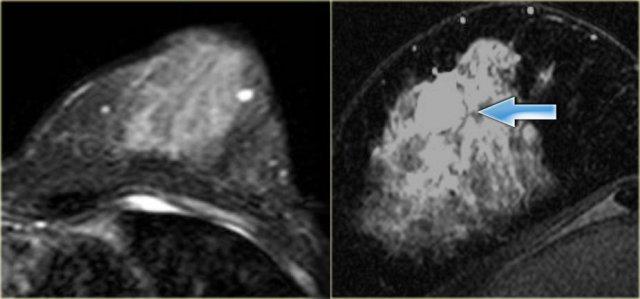

Ngấm thuốc viền ngoại vi

Hình ảnh bên trái cho thấy ngấm thuốc viền ngoại vi của một tổn thương xâm lấn mô xung quanh trong trường hợp ung thư biểu mô ống xâm nhập.

TRÁI: Ngấm thuốc không đồng nhất trong ung thư biểu mô ống tuyến xâm nhập PHẢI: Ngấm thuốc dạng chấm trong u hamartoma kèm thay đổi xơ nang (mũi tên)

Ngoài cùng bên trái là ngấm thuốc không đồng nhất trong ung thư biểu mô ống tuyến xâm nhập.

Hình ảnh kế bên cho thấy ngấm thuốc dạng chấm trong u hamartoma kèm thay đổi xơ nang (mũi tên).